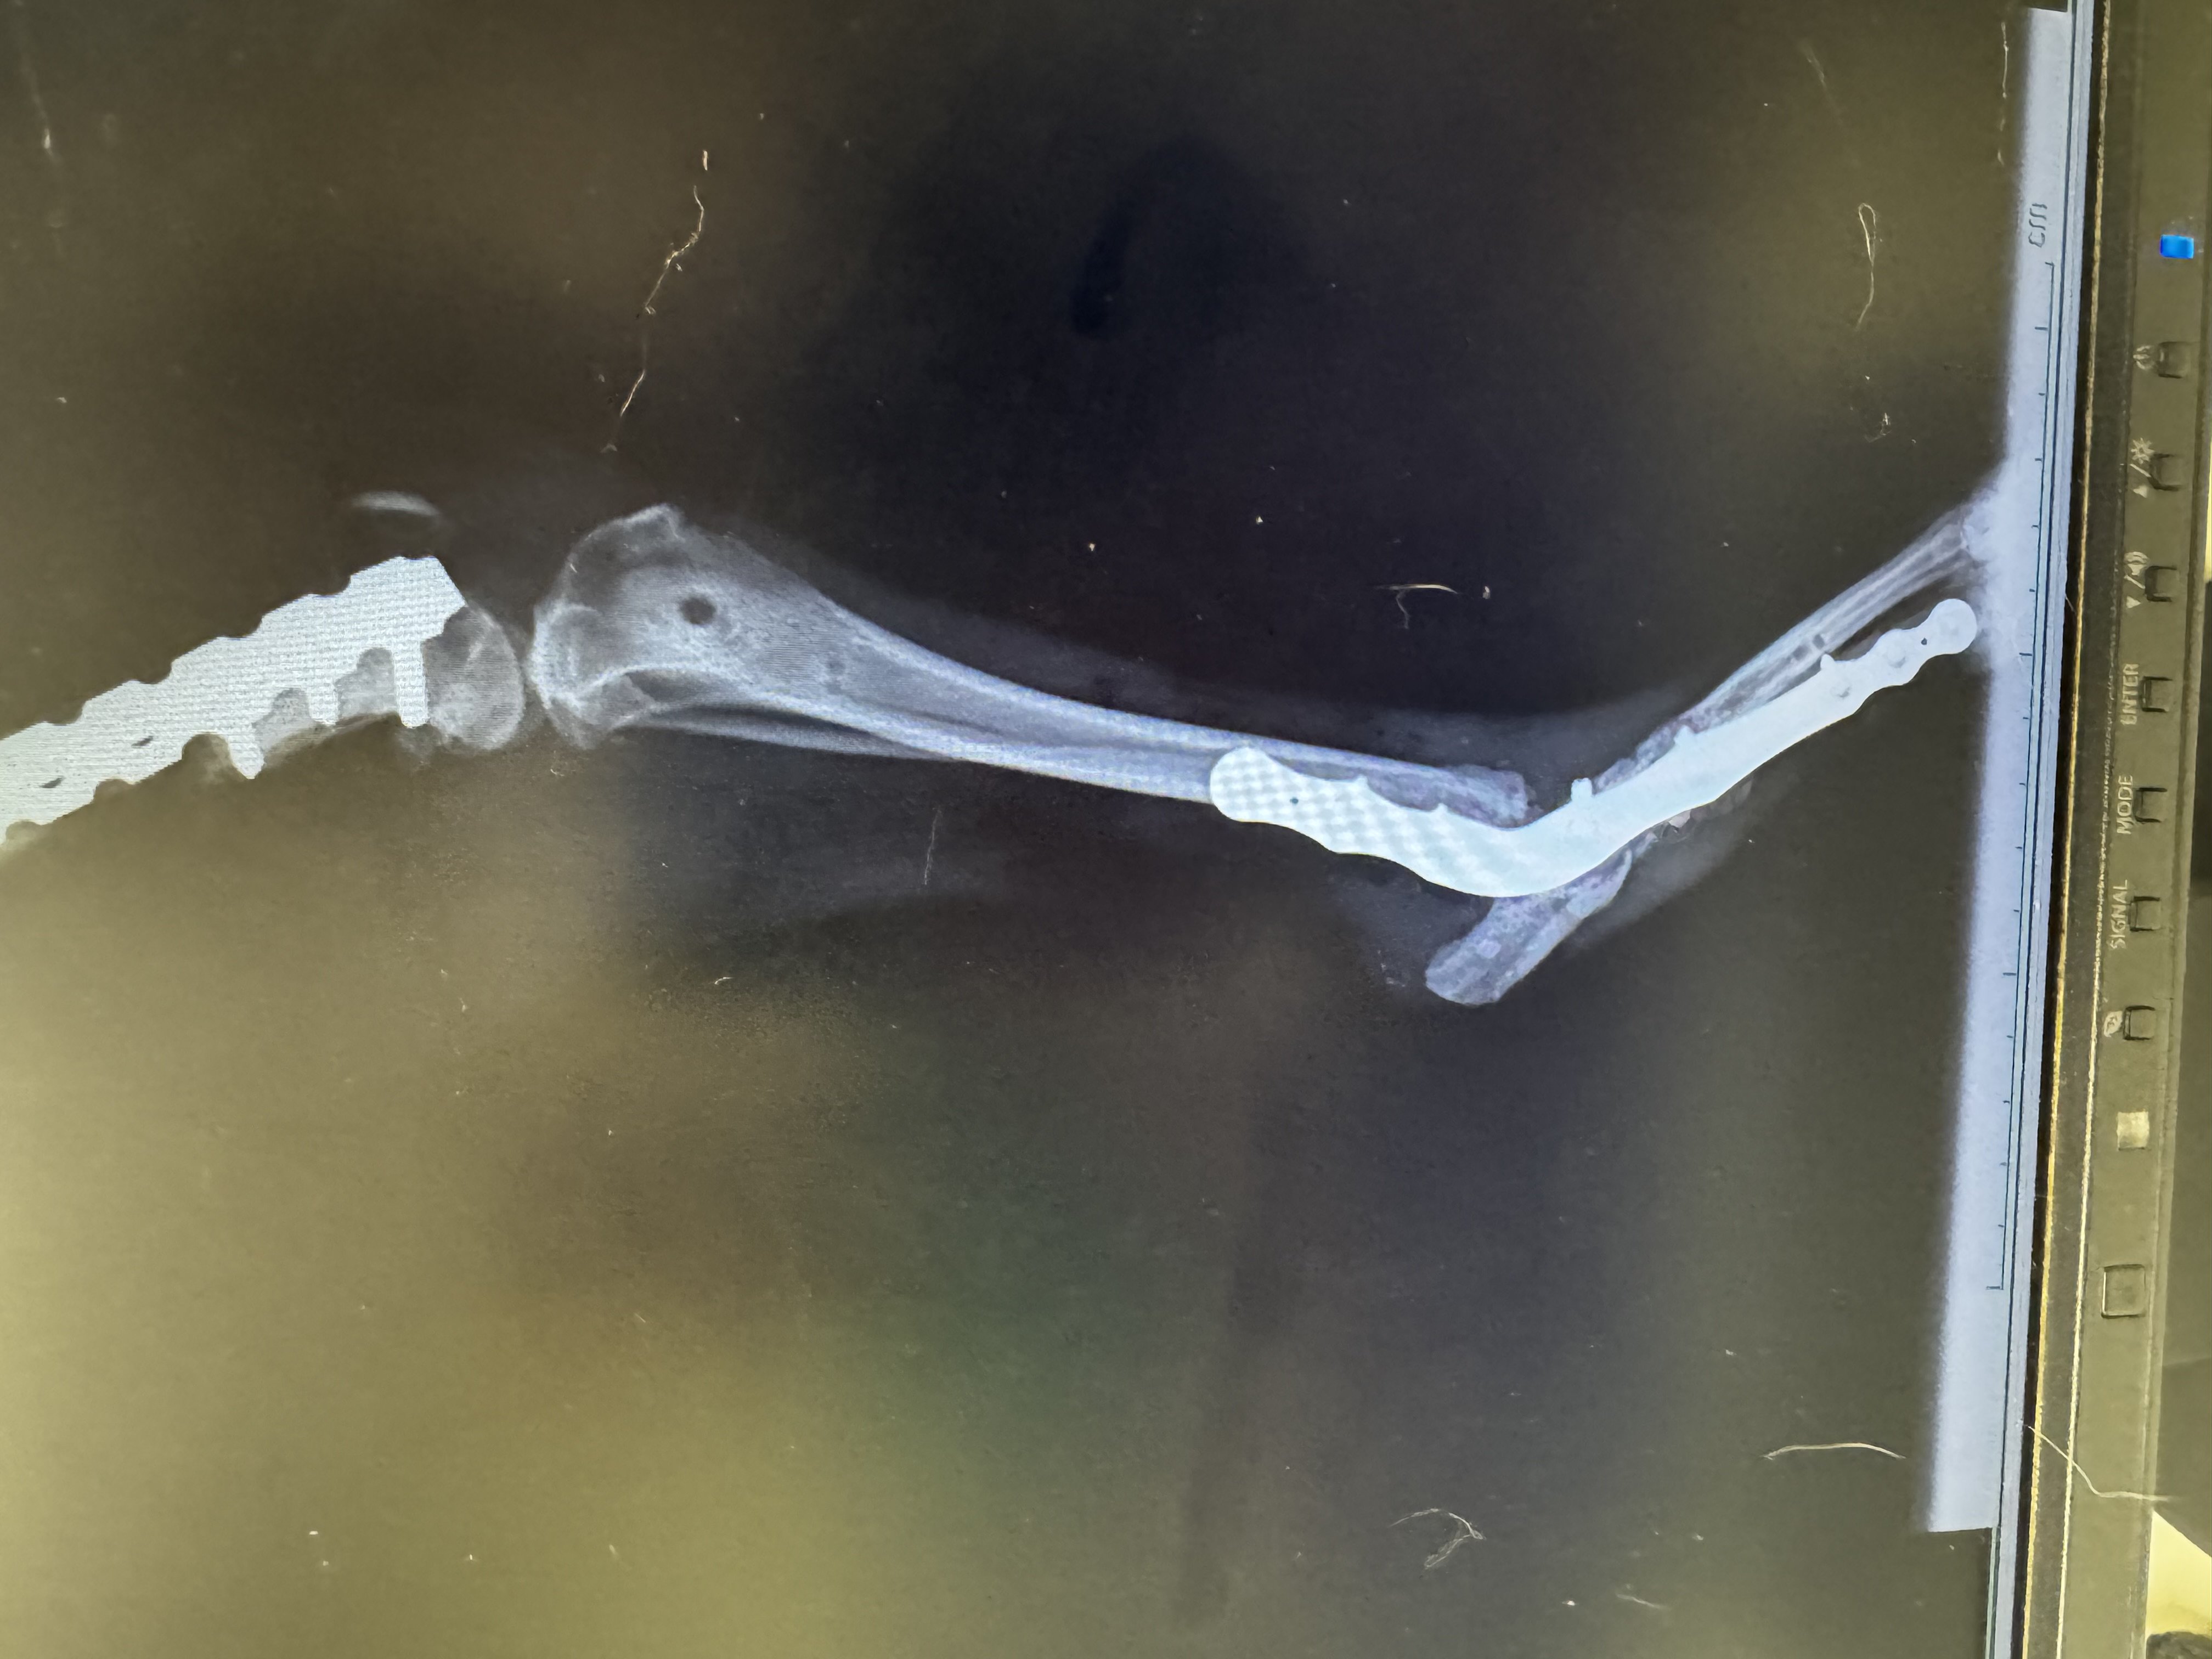

• Ieri lux ha fatto il secondo intervento ortopedico, quello di artrodesi del tarso. La chirurgia è andata bene ma purtroppo, a causa del prolungato inutilizzo e delle diverse chirurgie sul femore, il quadricipite si è contratto gravemente e quasi sicuramente non riuscirà più a piegare il ginocchio. Solo tanta tanta tanta fisioterapia potrebbe leggermente migliorare la situazione. Noi comunque non ci arrendiamo e andiamo avanti!!4AS4v9BkT25nW20o.jpgiAcrzkIBjV32Ctue.jpgnKBpBm89w3AwckH5.jpg4lVS96y6mWEZYS4s.jpg

Ciao a tutti, ci presentiamo. Siamo Giulio, Ilaria, Iside una border collie di 11 anni e Mizzi una meticcetta di 17 anni. Il nostro problema è che siamo stati rapiti da un musino dolcissimo di una cagnolina, abbandonata in clinica veterinaria dopo essere stata investita. I danni riportati purtroppo sono stati tanti: frattura scomposta con schegge di femore, varie fratture di bacino, frattura del tarso, un danno del nervo sciatico e diastasi sacro iliaca sull’altra zampa oltre che un importante scuoiamento di buona parte della schiena. Insomma, le cose da fare erano davvero tante, da non sapere da dove cominciare! Ma in qualche modo abbiamo fatto, noi abbiamo deciso che questa vita aveva ancora da dare tantissimo al mondo e ce la siamo intestata battezzandola così Lux. Lux è una cagnolina di 8 mesi, dolcissima e con tantissima voglia di vivere e ricominciare a correre. Grazie a tanti angeli la cute sulla schiena ha ricominciato a crescere, abbiamo iniziato con delle lunghe chirurgie ortopediche per cercare di sistemare quel che si poteva ma poi ci ha rallentato il tetano che ci ha messi a dura prova. Ma la forza d’animo di Lux non si è mai persa e nonostante tutto abbiamo passato anche questa! Ora però bisogna reintervenire sulle fratture e noi, suoi migliori amici umani, ci rendiamo conto che le spese da sopportare iniziano ad essere troppo gravose. Noi non vogliamo fermarci, ci crediamo davvero che Lux possa tornare un giorno a camminare e correre nei prati come probabilmente sogna anche lei quando si vedono le sue zampine fendere l’aria. Vi chiediamo quindi di credere con noi ed aiutarci a darle un futuro.